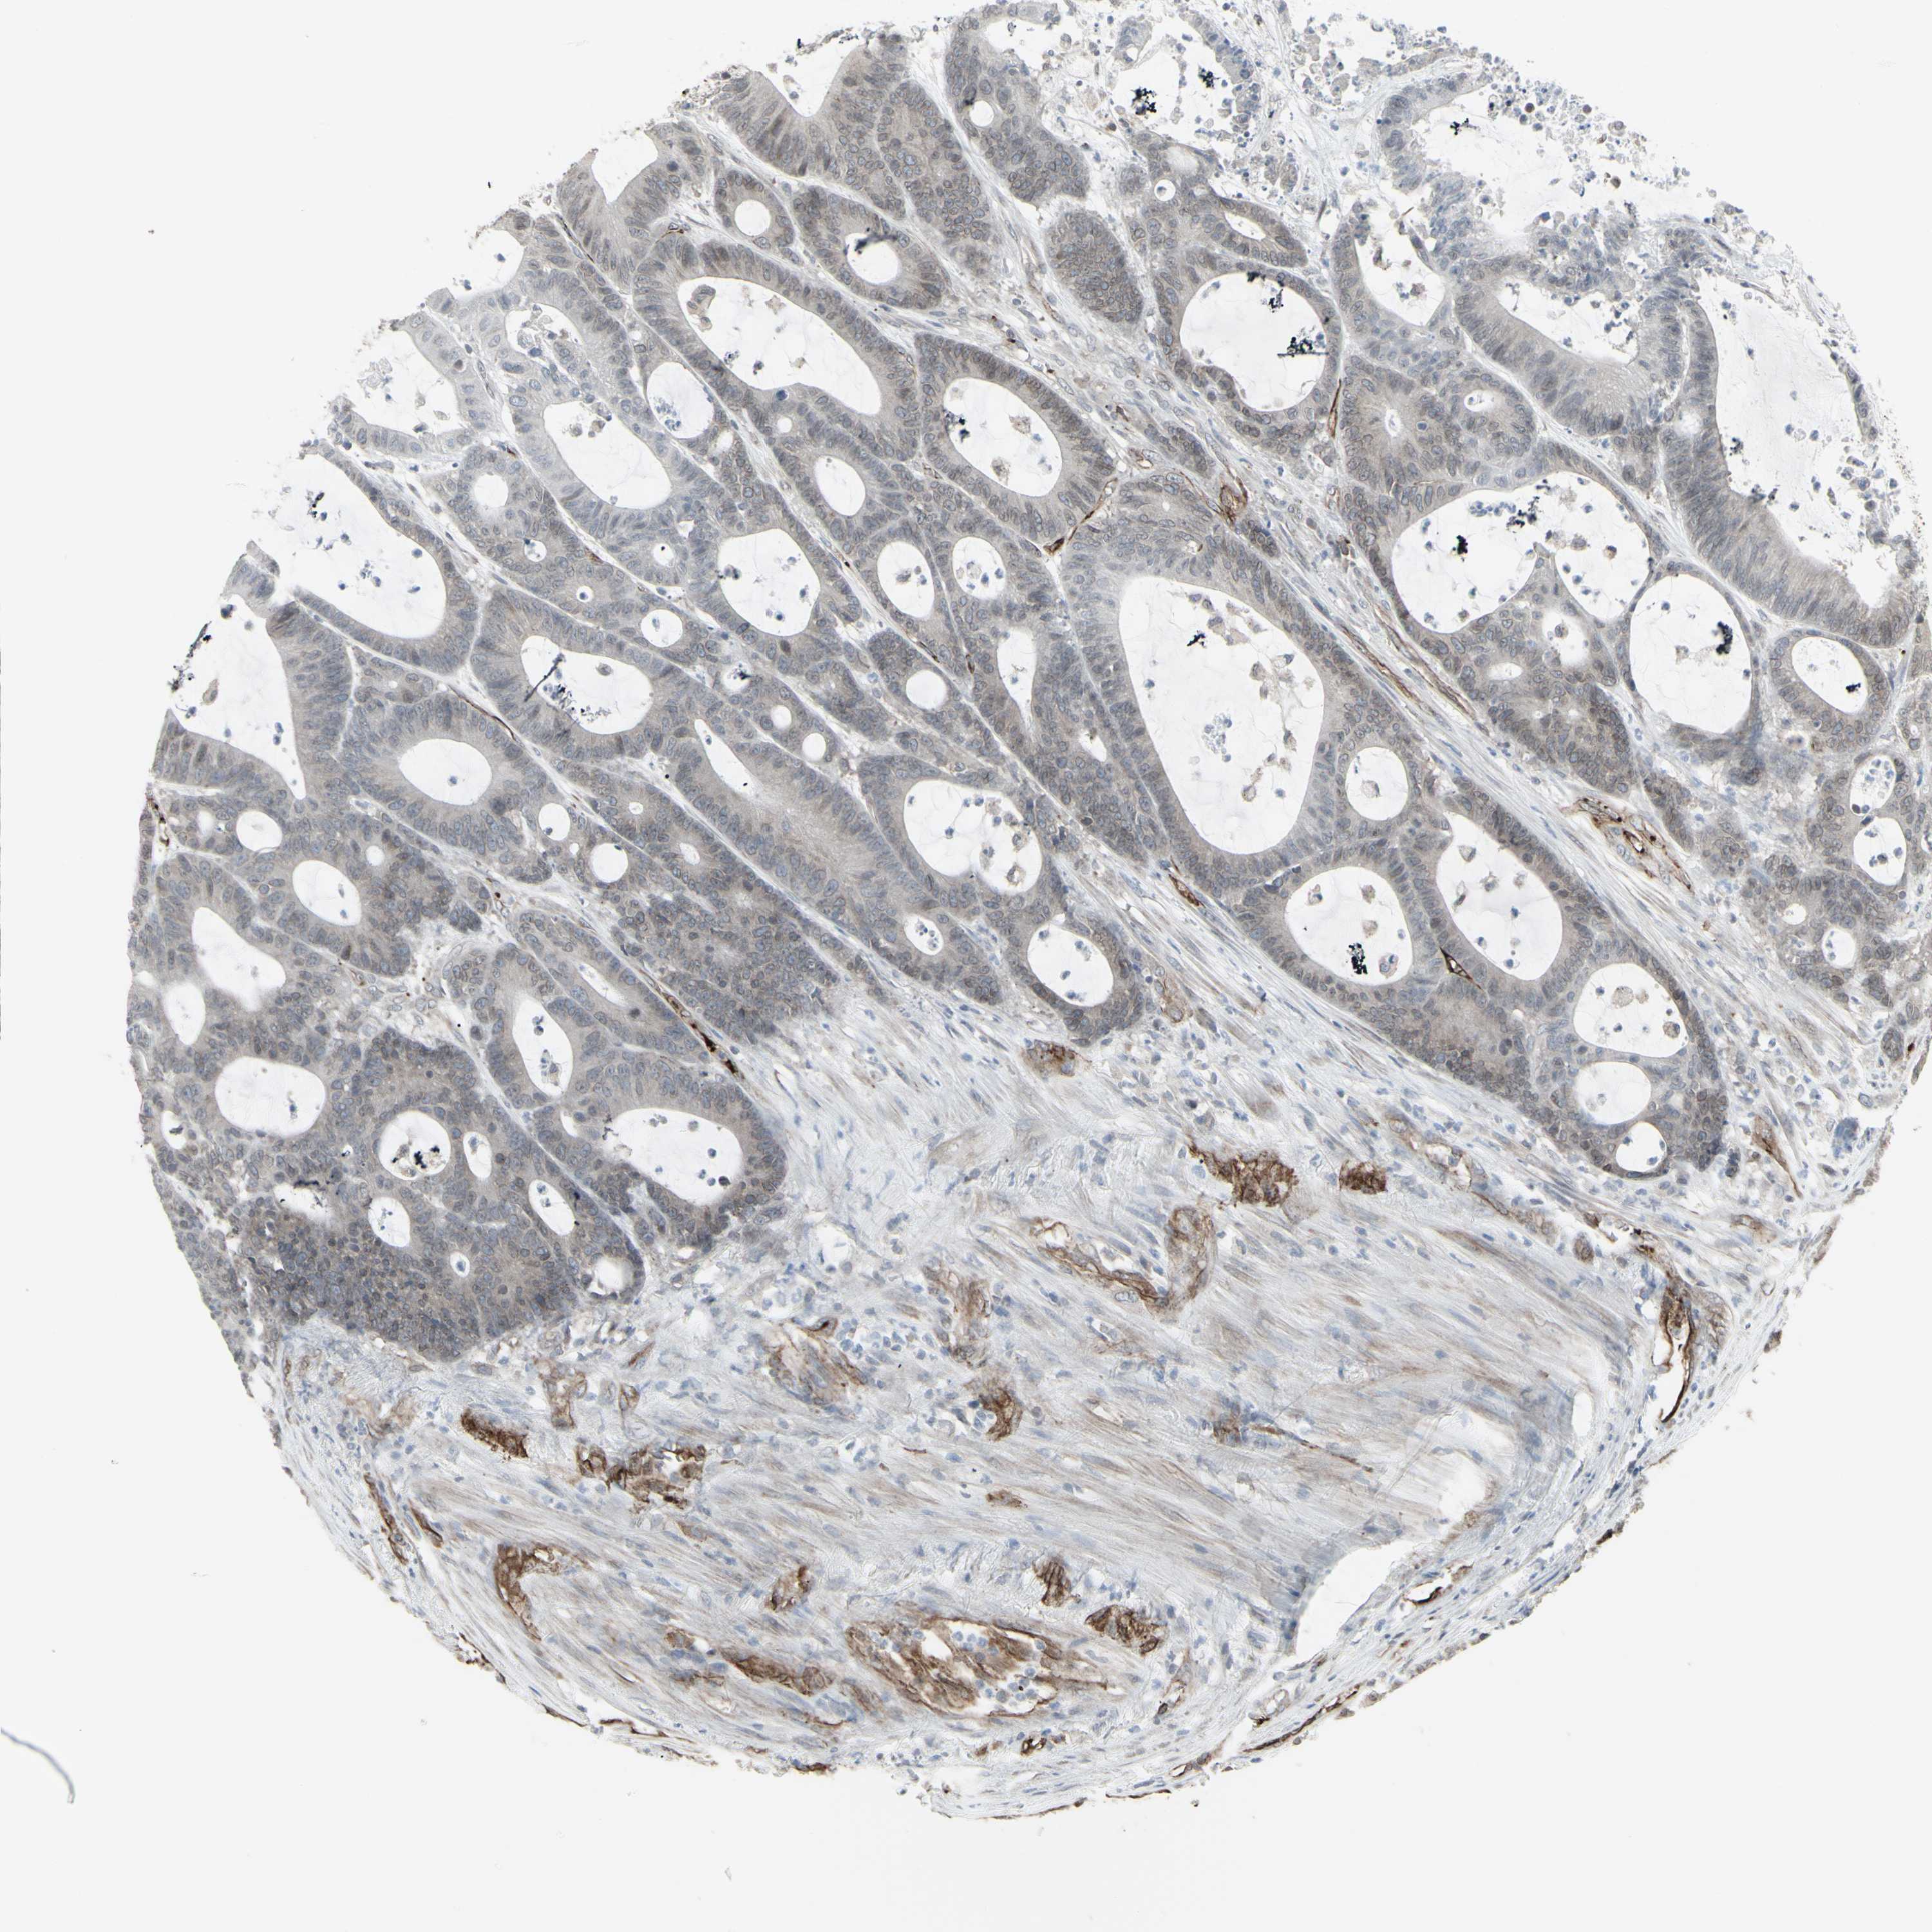

Colorectal cancer

Colon adenocarcinoma

Average pTPM 25.1

Number of samples 254